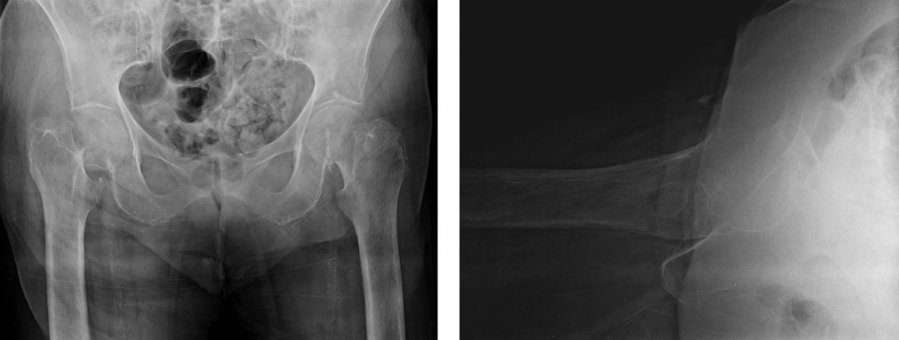

病例2:75岁女性,不慎从高出摔下致髋关节疼痛。

病史:慢性阻塞性肺疾病,并且夜间需要吸氧1 L;心房颤动(长期服用华法林);3期肾脏疾病;高血压; 黑色素瘤。

她有长期吸烟史(45包年),可正常从事日常生活,但在屋外活动需要使用拐杖。

研究人员对556名外科医生完成了在线调查,共有该调查包括两个部分:(1)外科医生的人口统计学信息;(2)要求对两个老年髋部骨折病例给出治疗决策。病例如上图所示。对股骨颈骨折的治疗考量和方案进行电子问卷调查,发出731份,收回有效问卷556份;其中390份医生经历关节外科训练、50份经历创伤骨科训练,该比例接近美国注册的比例(3156:619)。研究人员希望通过此研究对创伤骨科和关节外科医生进行调查,比较不同亚专业组间的培训及处理老年股骨颈骨折的差异,并将治疗方法与美国骨科医师学会临床实践指南进行比较。